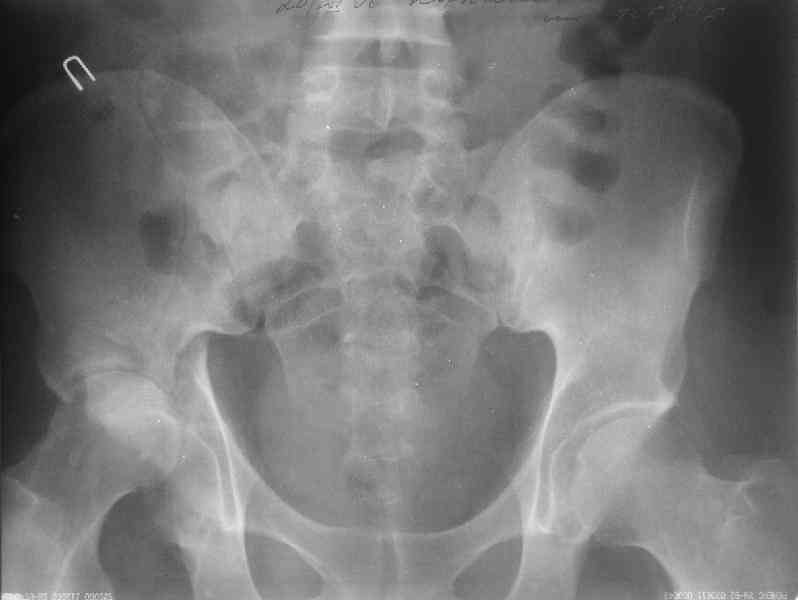

Уважаемы коллеги! Поступил непростой больной 24 лет через 1 месяц после травмы (фото в приложении). Кроме перелома правой вертлужной впадины, перелома и вывиха этого же бедра имеются переломы диафиза правой плечевой кости, диафиза правой локтевой кости, диафизов обеих костей левого предплечья.

Неврологии со стороны нижних конечностей нет. Планируем первым этапом выполнить ЗИМО длинных трубчатых костей. Вопросы: 1. имеет ли смысл в эти сроки идти на остеосинтез вертлужной впадины и вправление вывиха или планировать первичное эндопротезирование? 2. Есть у кого-нибудь ссылки или другая информация по поводу исходов лечения переломов вертлужной впадины, сопровождающихся вывихом головки бедра в разные сроки (буду очень признателен, если поделитесь)?A male 24 y.o, admitted to our unit today 1 month post injury - images attached. Except ipsilateral acetabular fx, femoral shaft fx and hip dislocation also he has shaft fxs of right humerus and ulna, left radius and ulna. No neurological deficits after the hip dislocation. At first we plan closed nailing of all long bones. Questions are regarding the acetabular fx + dislocation. With the 1 month of exposition and obvious callus everywhere does it make sense to attempt ORIF of the acetabulum with hip reduction, or primary THA should be considered? Does anybody have references on outcomes after delayed surgeries for acetabular fx + hip dislocation depending on duration of the delay? С уважением Максим Агалаков, УНИИТО Е-бург.